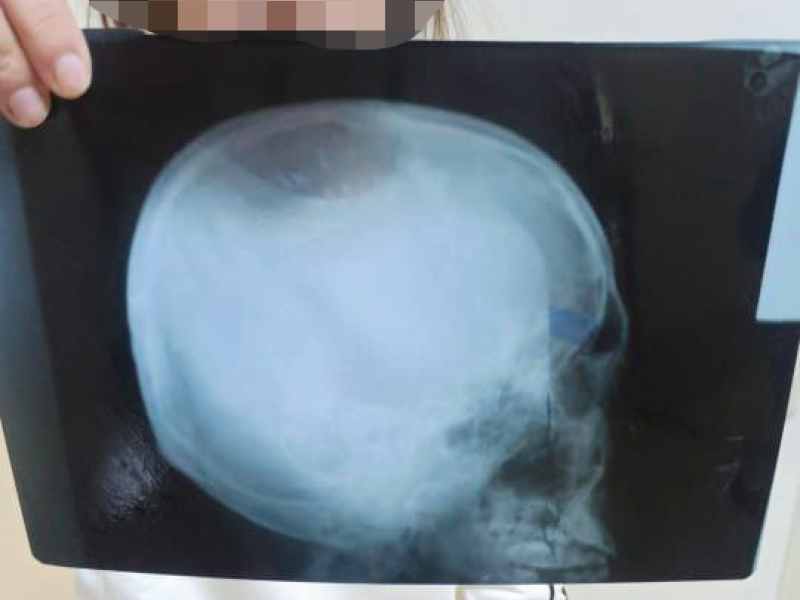

После чего сотрудник Акыйкатчы КР и клинический руководитель приехали вместе с потерпевшей в городскую прокуратуру, где она оставила разъяснительное письмо с приложением Стамбульского протокола. 04.10.22 года прокуратурой г. Ош вынесено постановление о назначении судебно-медицинской экспертизы. В настоящее время, ведутся следственные мероприятия и проводится медицинское обследование гр. Б.Э. по вышеуказанному постановлению.